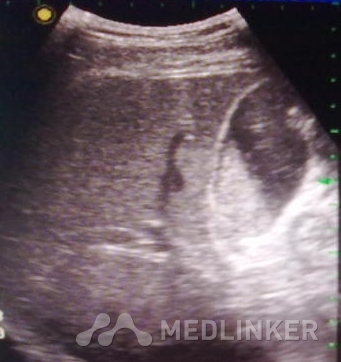

胆囊结石漏诊的原因: 胆囊颈部结石;特殊类型的胆囊结石,超声表现不典型,如泥沙样结石、充满型结石;或由于胆囊萎缩导致显示不清;伪像干扰;仪器调节不当等等; 误诊原因有:胆泥、胆汁粘稠、胆囊壁息肉、胆囊壁颈部褶皱、血凝块、胆囊内气体、药物性胆囊结石等; 如何提高超声诊断正确率?

熟悉胆道系统超声解剖,包括胆囊和胆管的超声解剖;

正确认识上述提到的漏诊与误诊原因;

提高检查手法,能针对不同的胆道解剖结构,采用不同超声显示切面